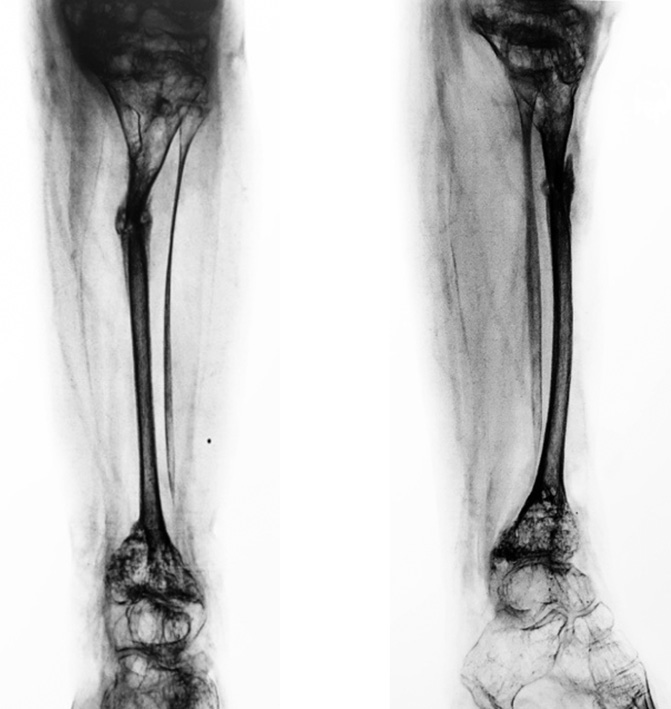

On the control radiograph of the lower leg bones, performed a month after the surgery, bone callus formation was noted in the proximal part of the right tibia, and the patient had a fracture of the tibia at the level of the formed regenerate (Fig. 10).

Fig. 10. Radiographs of the right tibia bones in two views 1 month after dismantling the external fixation device

The situation analysis revealed that refracture could occur because of a change in pressure on the bone after dismantling the EFD and during the removal of casts in orthosis manufacture.